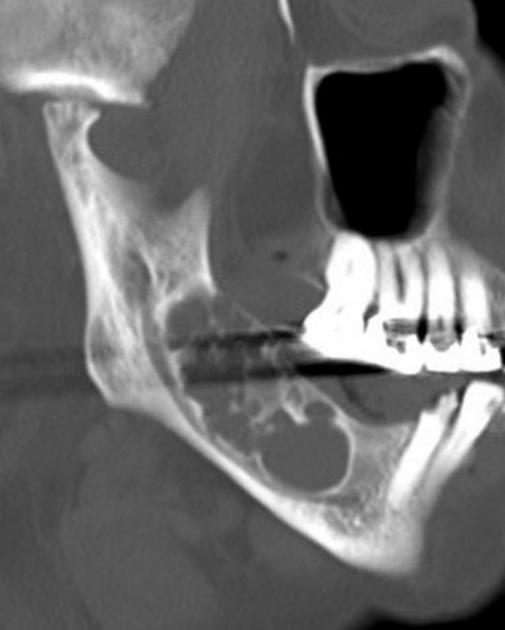

Ameloblastoma